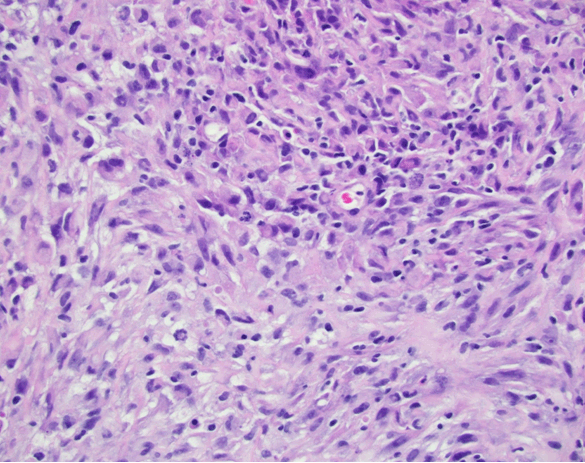

A 62-year-old male presented to his primary care physician's office with one-month duration of difficulty moving bowels, bloating, and abdominal pain. Abdominal computed tomography (CT) scan revealed rectal thickening concerning for malignancy with metastatic lymphadenopathy and a right upper quadrant 20 cm mass centered in the left lobe of the liver. Biopsy of sigmoid colon showed invasive moderately differentiated adenocarcinoma (Figure 1). Pre-colonoscopy laboratory evaluation at this visit demonstrated an elevated calcium level (Table 1). Five days following colonoscopy, the patient presented to the emergency department with right lower extremity cellulitis leading to hospitalization and septicemia. Due to concern for liver abscess, the liver mass was biopsied. Pathology showed high-grade epithelioid mesothelioma (Figure 2). During the hospitalization, his calcium levels rose (Table 1) and workup for the etiology of hypercalcemia began (Table 2). There was no evidence of osteolytic lesions on imaging, serum and urine electrophoresis were negative, and thyroid-stimulating hormone was within normal limits. There was also no evidence of granulomatous disease or evidence of granulomatous infection on imaging studies. Bisphosphonate administration brought the patient's calcium level to within normal range (Table 1). His hospital course continued due to septicemia and renal failure requiring dialysis. He was eventually transferred intensive care unit because of hypotension and septic shock from Escherichia coli bacteremia secondary to right leg cellulitis. Despite being on 3 vasopressors, antibiotics, and continuous renal replacement therapy, his condition deteriorated and patient died on comfort measures.

Figure 1: Sigmoid biopsy in formalin showing invasive moderately differentiated adenocarcinoma. Depth of involvement could not be determined.

Figure 2: Liver core biopsy showing high grade malignant neoplasm consistent with epitheloid mesothelioma. Immunoperoxidase stain for inhibin, CAM 5.2, CK7, calretinin, WT1 were positive. This malignant neoplasm is histologically distinct from the patient's rectal adenocarcinoma and represents a synchronous secondary primary neoplasm.